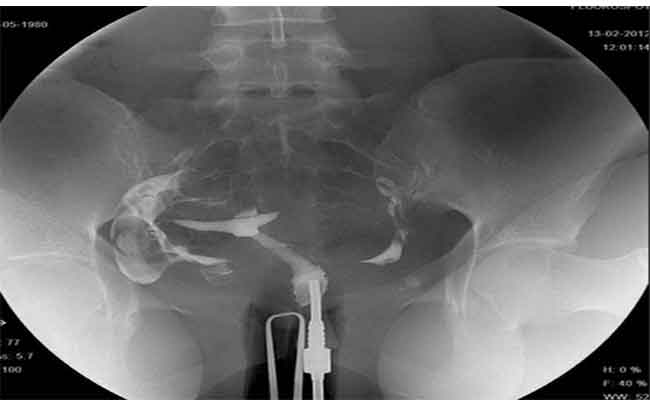

كيف يمكن ان تضرّ اشعة الصبغة الرحم؟

يمكن لأخصائي الأشعة مشاهدة الصبغة وهي تتحرك عبر جهازك التناسلي. سيتمكن بعد ذلك من معرفة ما إذا كان لديك انسداد…